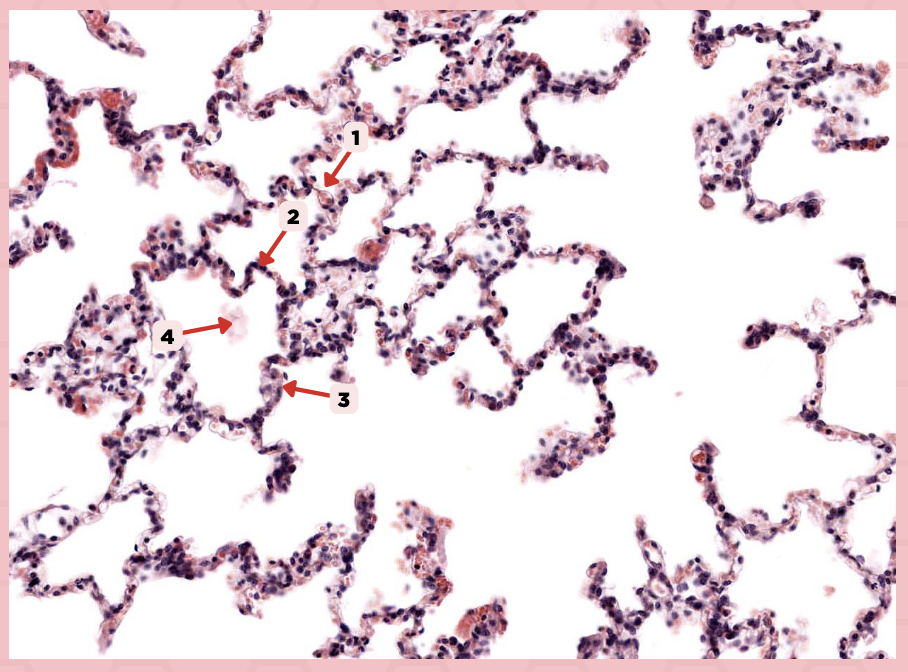

Lumens and Interalveolar septa

Name the irregular spaces and the fine threads of tissue that separate them.

Interalveolar septa

Identify the structure labeled as 1.

Type 1 and Type 2 Alveolar Cells

What are the 2 cell types for alveoli?

Simple squamous epithelium

What kind of epithelium are these alveolar cells?

Interalveolar septum

Identify the structure labeled as 1.

Type I alveolar cell

Identify the structure labeled as 2.

Type II alveolar cell

Identify the structure labeled as 3.

Pulmonary Alveolar Macrophages (Dust Cells)

Identify the structure labeled as 4.

Pulmonary Alveolar Macrophages (Dust Cells)

What are the most numerous cells inside the alveoli?

Pneumocyte Type I

Which of the following labeled structures covers 95% of the alveolar surface?